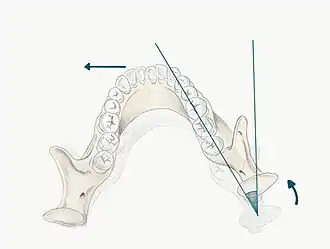

- Lateral movements: When the mandible moves to the left or right, the mandibular posterior teeth move laterally across the opposing teeth. For example, when the mandible moves to the right, the right mandibular teeth move laterally across their opponents and this is termed the working side of the mandible (the side towards which the mandible is moving). In contrast, the left mandibular teeth move medially, downwards and anteriorly across their opposing posteriors and this is called the non-working side (the side to which the mandible is moving away from).

Lateral excursions

It is important to define the movement of the condyles in lateral excursions:

- Working condyle: This is the condyle closest to the side which the mandible is moving (e.g. if the mandible moves laterally to the right, the right condyle is the working side condyle)

- Non-working condyle: This is the side to which the mandible is moving away from (e.g. if the mandible moves laterally to the right, the left condyle is the non-working side condyle)

- The maximum lateral movement of the mandible to the left or right side is approximately 10-12mm[2]

- The primary movement in lateral excursions occurs on the non-working side (NWS) condyle (also called the balancing or orbiting condyle). The NWS condylar head moves in a downward, forward and medial direction. This movement is defined against two separate planes, the vertical and horizontal plane

- Bennet Angle : the angle of medial movement on NWS condyle relative to the vertical plane

- Condylar Angle : the angle of downwards movement of the NWS condyle relative to the horizontal plane

- The working side (WS) condyle (also called the rotating condyle) undergoes an immediate, non-progressive lateral shift. This movement is called the Bennet movement (however this may be confused with the Bennet Angle), so this is more commonly referred to as an Immediate Side Shift. The condyle is seen to rotate with a slight lateral shift in the direction of movement[6]